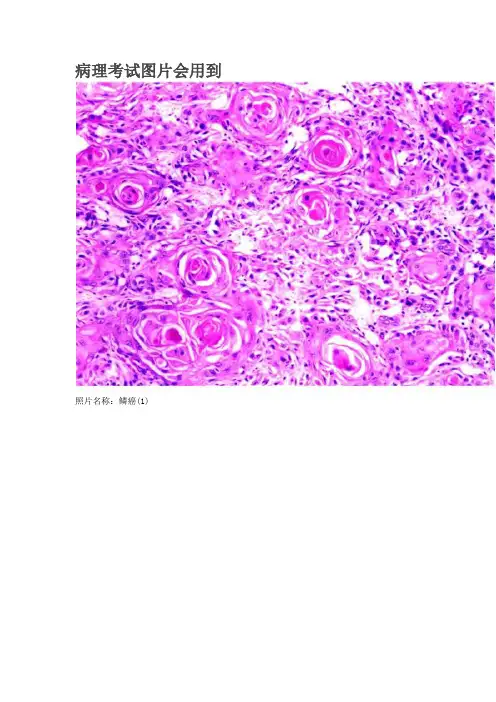

病理考试图片会用到照片名称:鳞癌(1)照片名称:风湿性心内膜炎(1)照片名称:肾结核(1)照片名称:肾癌(1)照片名称:肺淤血1照片名称:肺癌照片名称:肺结核(1)照片名称:肾水肿(1)照片名称:肺淤血(1)照片名称:肺梗死(1)照片名称:门脉性肝硬化(1)照片名称:肝水肿(1)照片名称:流脑照片名称:溃疡型胃癌照片名称:玻璃样变(1)照片名称:肉牙组织(1)照片名称:大叶性肺炎1照片名称:急性弥漫性增生性肾小球肾炎(1)照片名称:慢性肾小球性肾炎(1)照片名称:槟榔肝照片名称:硅肺??照片名称:动脉粥样硬化?血栓?照片名称:肠出血性梗死照片名称:子宫平滑肌瘤照片名称:肠息肉照片名称:大红肾蚤咬肾照片名称:细菌性心内膜炎照片名称:胃溃疡照片名称:胃溃疡照片名称:风湿性心外膜炎绒毛心照片名称:急性肝炎照片名称:髓质型照片名称:慢性肝淤血照片名称:纤维肉瘤照片名称:??急性肾小球肾炎照片名称:甲状腺肿大?照片名称:腺癌照片名称:肺气肿?照片名称:??肾小球肾炎照片名称:肾结核照片名称:周围型肺癌?照片名称:慢性肾小球肾炎照片名称:脂肪瘤照片名称:细菌性痢疾?照片名称:高血压心脏病照片名称:急性肝脓肿照片名称:蕈伞型胃癌?照片名称:卵巢畸胎瘤照片名称:脂肪肝照片名称:肾盂积水照片名称:高血压心脏病照片名称:颗粒性固缩肾?照片名称:原发型肝癌巨块型照片名称:肝硬化照片名称:慢性肾盂肾炎。